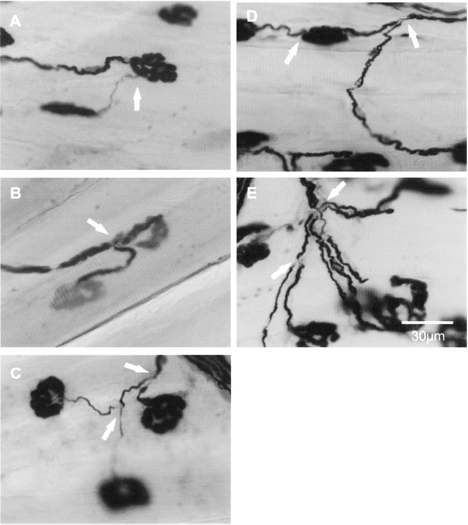

Axonal sprouting generally occurs when there is a loss of motorneurons due to trauma. It is a process in which nerves sprout from intact axons at either the motor endplates to give rise to ultraterminal sprouts, or the nerve terminals to give rise to preterminal sprouts, or to the nodes of Ranvier to give rise to nodal sprouts. Figure 1 shows the three previously discussed types of axonal sprouts.

Figure 1. Three different types of axonal sprouts commonly seen in partially denervated muscles. Panel A, B and C respectively show ultraterminal, preterminal and nodal sprouts as indicated by the arrows. In extensively denervated muscles, more complicated sprouting was observed: Panel D) 2 types of axonal sprouts (axonal and ultraterminal sprouts, indicated by arrows) emerged from a single axon; Panel E) multiple axonal sprouts (pointed by arrows) emerged from the same axon.